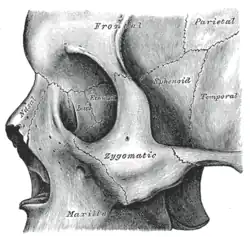

Osso zigomático esquerdo. Superfície de Malar.

Osso zigomático esquerdo. Superfície de Malar. Osso zigomático esquerdo. Superfície temporal.

Osso zigomático esquerdo. Superfície temporal. Visão lateral do crânio.

Visão lateral do crânio. Fossa infratemporal esquerda.